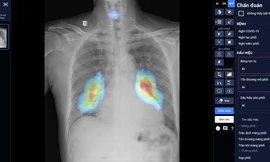

Trí tuệ nhân tạo – “trợ lý” đắc lực trong nỗ lực xây dựng Y tế số

Trong một tháng vừa qua, nhiều bệnh viện trung ương tuyến đầu đã đồng loạt triển khai sản phẩm ứng dụng trí tuệ nhân tạo (AI) do công ty VinBrain phát triển vào hỗ trợ các hoạt động Y tế. Điều này cho thấy xu hướng chung của các Bệnh viện trong việc phát triển và ứng dụng AI nhằm chung tay hướng tới một nền y tế số hiện đại, bình đẳng, văn minh.